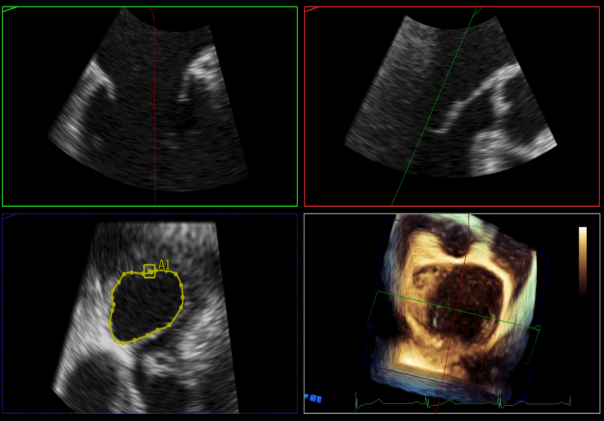

瓣叶捕获后,前叶抓捕长度9.1mm,后叶抓捕长度7.8mm

外侧残余少量分流

第一个夹子外侧残余小脱垂

残余分流主要来源于残余脱垂区域

评估瓣口条件,平均跨瓣压差:2mmHg,决定在第一个夹子外侧下第二个夹子

第一个夹子外侧放第二个夹子

第二个夹子捕获瓣叶后,前叶抓捕长度9.3mm,后叶抓捕长度7.3mm

未见明确残余分流

三维评估两个夹子位置

3D-color再次确定未见残余分流

评估瓣口条件,平均跨瓣压差:4mmHg

肺静脉血流频谱恢复正常